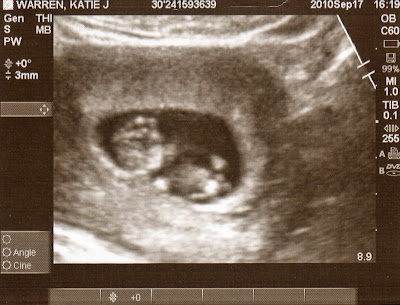

Last Friday I was able to meet baby Warren for the first time. I saw baby's hands and feet, head and belly. When I saw baby's heart beating in its chest I literally laughed out loud. The nurse quickly told me not to laugh because it messed her picture up and we had to find the little one all over again. I was even able to hear baby's heart beat, which was so encouraging because it sounded quick and strong. When I saw the baby moving around it made me so joyful that we've come this far already together and I hope you guys will keep praying for the baby's development and health. I can't believe I have the honor and blessing of having this miracle take place inside me. Here's a picture for you all to see!

From left to right is the head and then the hands and feet. Look at the baby's cute belly!